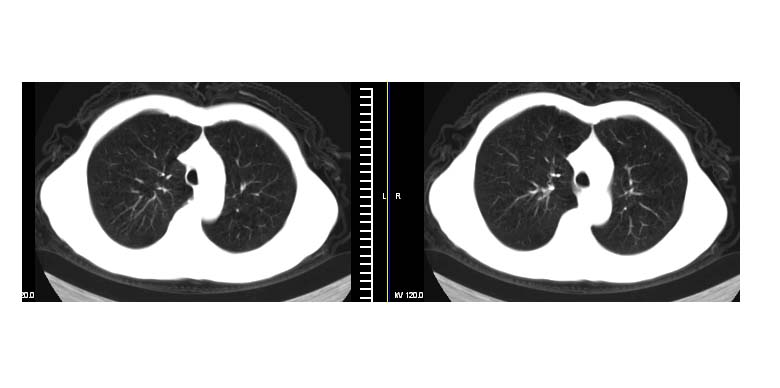

标题: CT11019:男性,66岁。发烧5-6天。治疗后无明显好转。 [打印本页]

标题: CT11019:男性,66岁。发烧5-6天。治疗后无明显好转。

左下肺中央型肺癌伴阻塞性肺炎\\肺不张可能性大,建议支纤镜检查.

1.左肺门似可见一小块影,由此考虑中央型肺ca并阻塞性肺炎改变;

2.左下叶背段肺tb(干酪性肺炎)?

3.单纯肺感染?建议进一步检查。

左肺门下分增大见有结节影,基底干及分支显示不清,下叶体积缩小,呈片带状机磨玻璃样影显示。支持考虑左下肺中心型肺癌伴阻塞性肺炎及部分肺不张。建议纤支镜检查